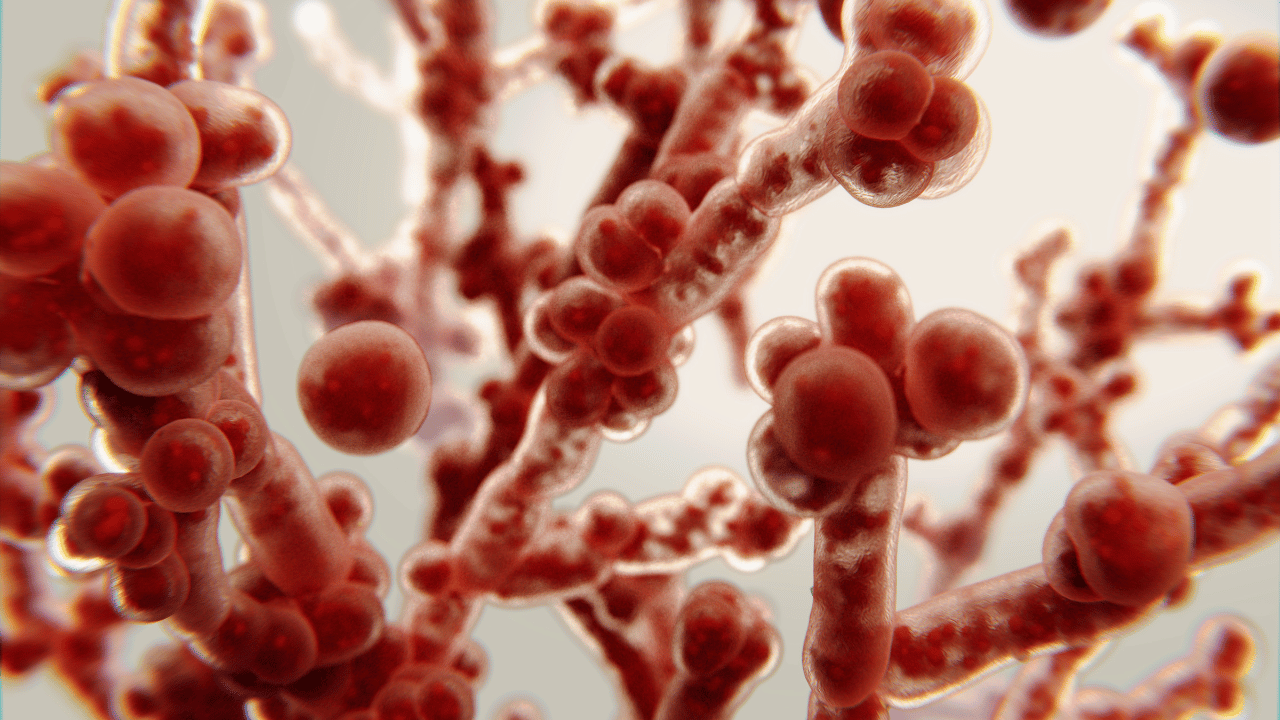

Sentir coceira, ardência e desconforto na região íntima já é algo bastante incômodo. Agora imagine quando isso começa a acontecer com frequência. Muitas mulheres tratam,